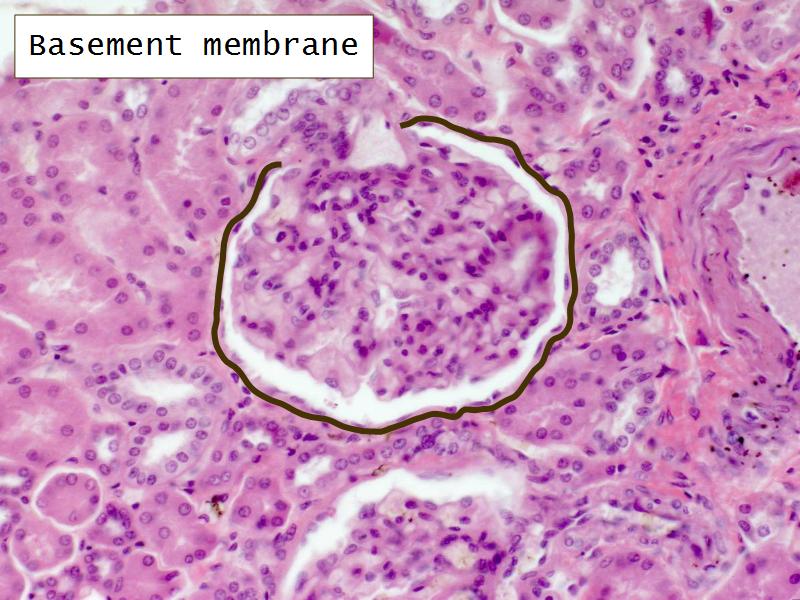

- The renal corpuscle

- Complete the drawings for each slide in the practical workbook.